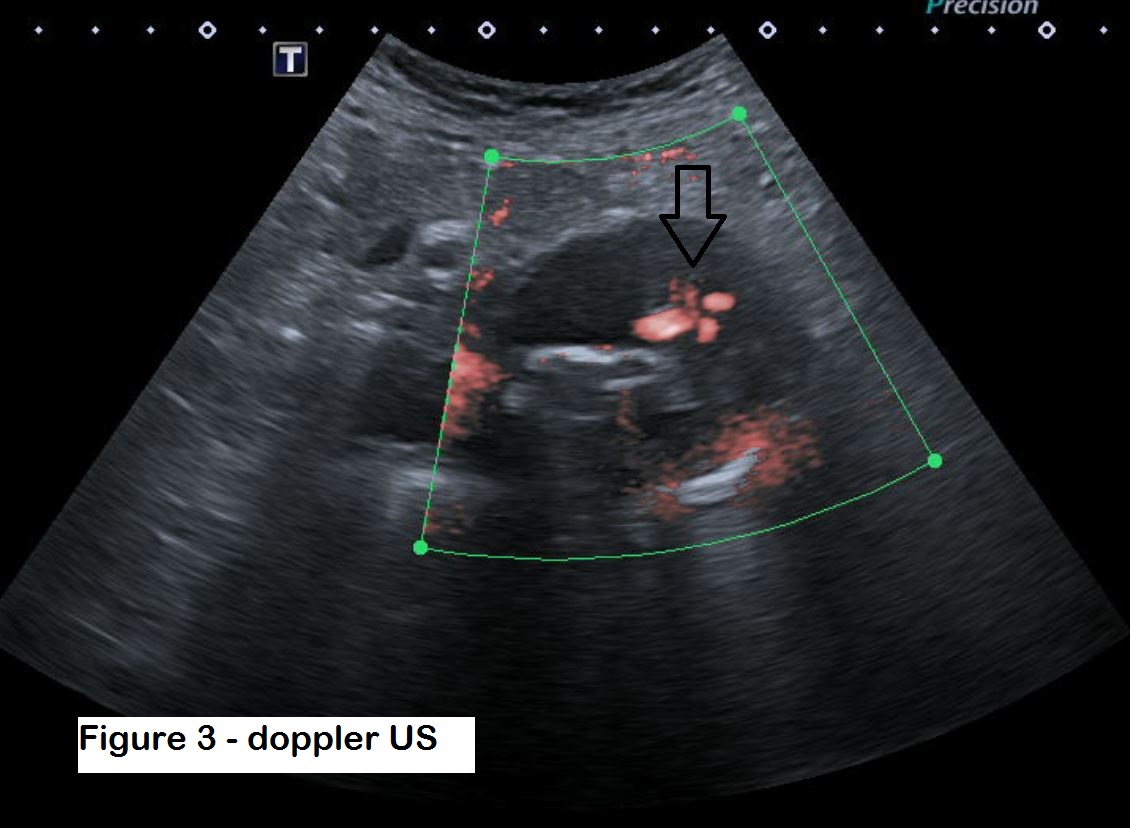

Figure 3: Doppler ultrasound shows flow within the aneurysm sac